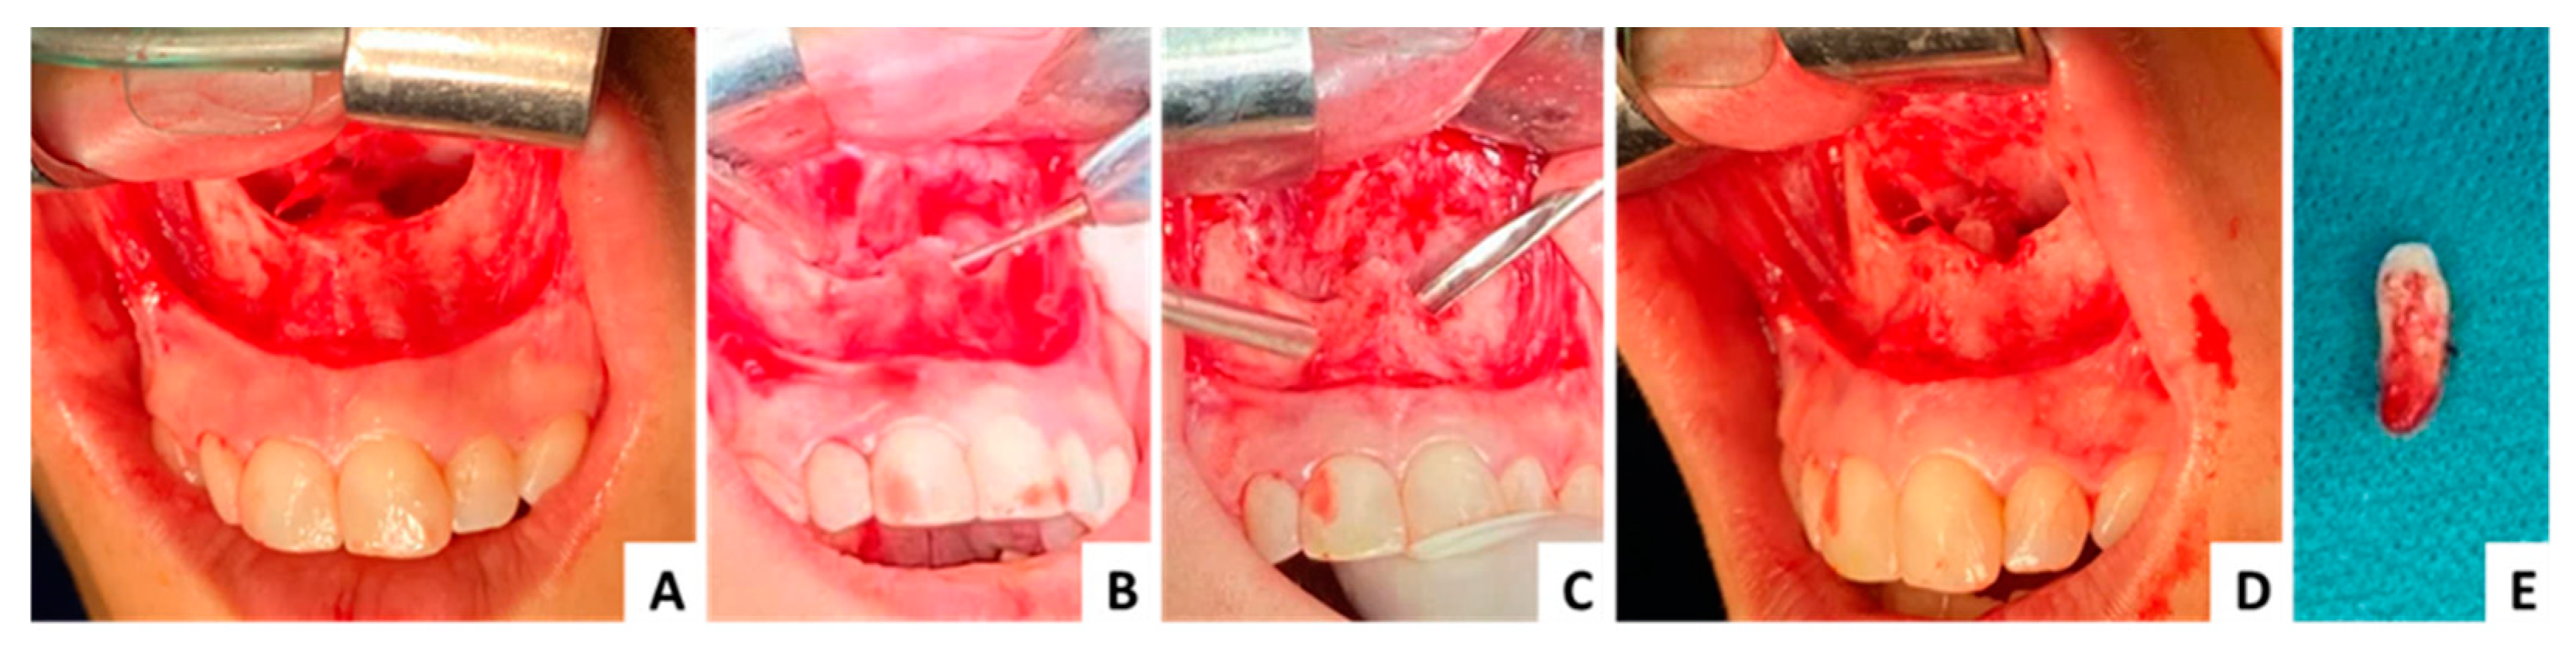

3.1. Case 1 (Figure 3, Figure 4 and Figure 5)